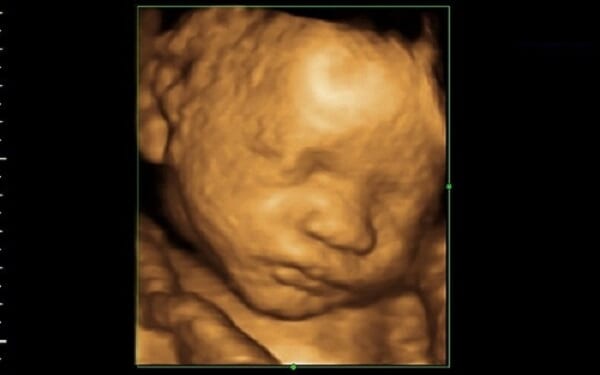

licensed to practice in South Carolina. South Carolina law requires an abortionist to be licensed in South Carolina, obtain informed consent from a woman seeking abortion, examine her in person, perform an ultrasound, and offer information on alternatives to abortion. Mail-order abortion drugs circumvent South Carolina’s protective laws, Mrs. Van Riper said.